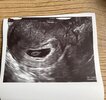

Dziewczynki ja po wizycie jest serduszko🥹❤️❤️ Z om 7+5 z usg 6+4 (podobno to normalne ale nie wiem, na usg prawie 2 tyg temu był tylko 1 dzień różnicy..) kartę ciąży mam wizyta następna za miesiąc❤️ Jeszcze kilka badań do zrobienia mi zostało ale witaminy które biorę są wystarczające i nic więcej nie trzeba🥰 tsh mi spadło do 5,5 chociaż to i tak bardzo dużo ale na początku czerwca było 7.78 wiec idziemy w dobrym kierunku

A i pani okazała się bardzo miła i kochana nie to co ta ostatnio i jak mnie zobaczyła to stwierdziła ze jestem taka chudzina ze pewnie cc będzie😂

• 62DC2EE2-E43C-4B54-8B63-6F092FAA082E.jpeg

62DC2EE2-E43C-4B54-8B63-6F092FAA082E.jpeg

638,5 KB · Wyświetleń: 96